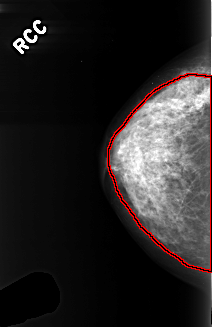

FILE: C_0366_1.RIGHT_CC.OVERLAY

TOTAL_ABNORMALITIES 1

ABNORMALITY 1

LESION_TYPE CALCIFICATION TYPE PLEOMORPHIC DISTRIBUTION DIFFUSELY_SCATTERED

ASSESSMENT 3

SUBTLETY 3

PATHOLOGY BENIGN

TOTAL_OUTLINES 1

BOUNDARY